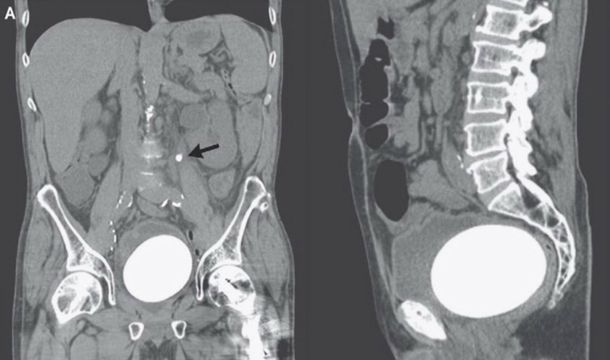

Un hombre de California, en los Estados Unidos, fue al médico por un dolor constante en la zona baja del abdomen y problemas para orinar y los médicos descubrieron que tenía una piedra de 770 gramos alojada en la vejiga.

La mayoría de las piedras que se forman en el riñón o la vejiga son tan pequeñas que el cuerpo las puede expulsar por las vías naturales -aunque sea con un poco de dolor- pero en el caso de este paciente de 64 años el bulto tenía el tamaño y la forma de un huevo de avestruz, informó el sitio Daily Mail.

Los médicos tuvieron que remover de manera quirúrgica la piedra así como también destruyeron con un láser una pequeña formación mineral en el uréter, el conducto por el que desciende la orina desde el riñón a la vejiga.

Se cree que la mega piedra se formó debido a que el hombre había sufrido cáncer de vejiga hace una década y los médicos tuvieron que construirle una nueva a partir de sus intestinos, lo que aumenta dramáticamente la formación de piedras.